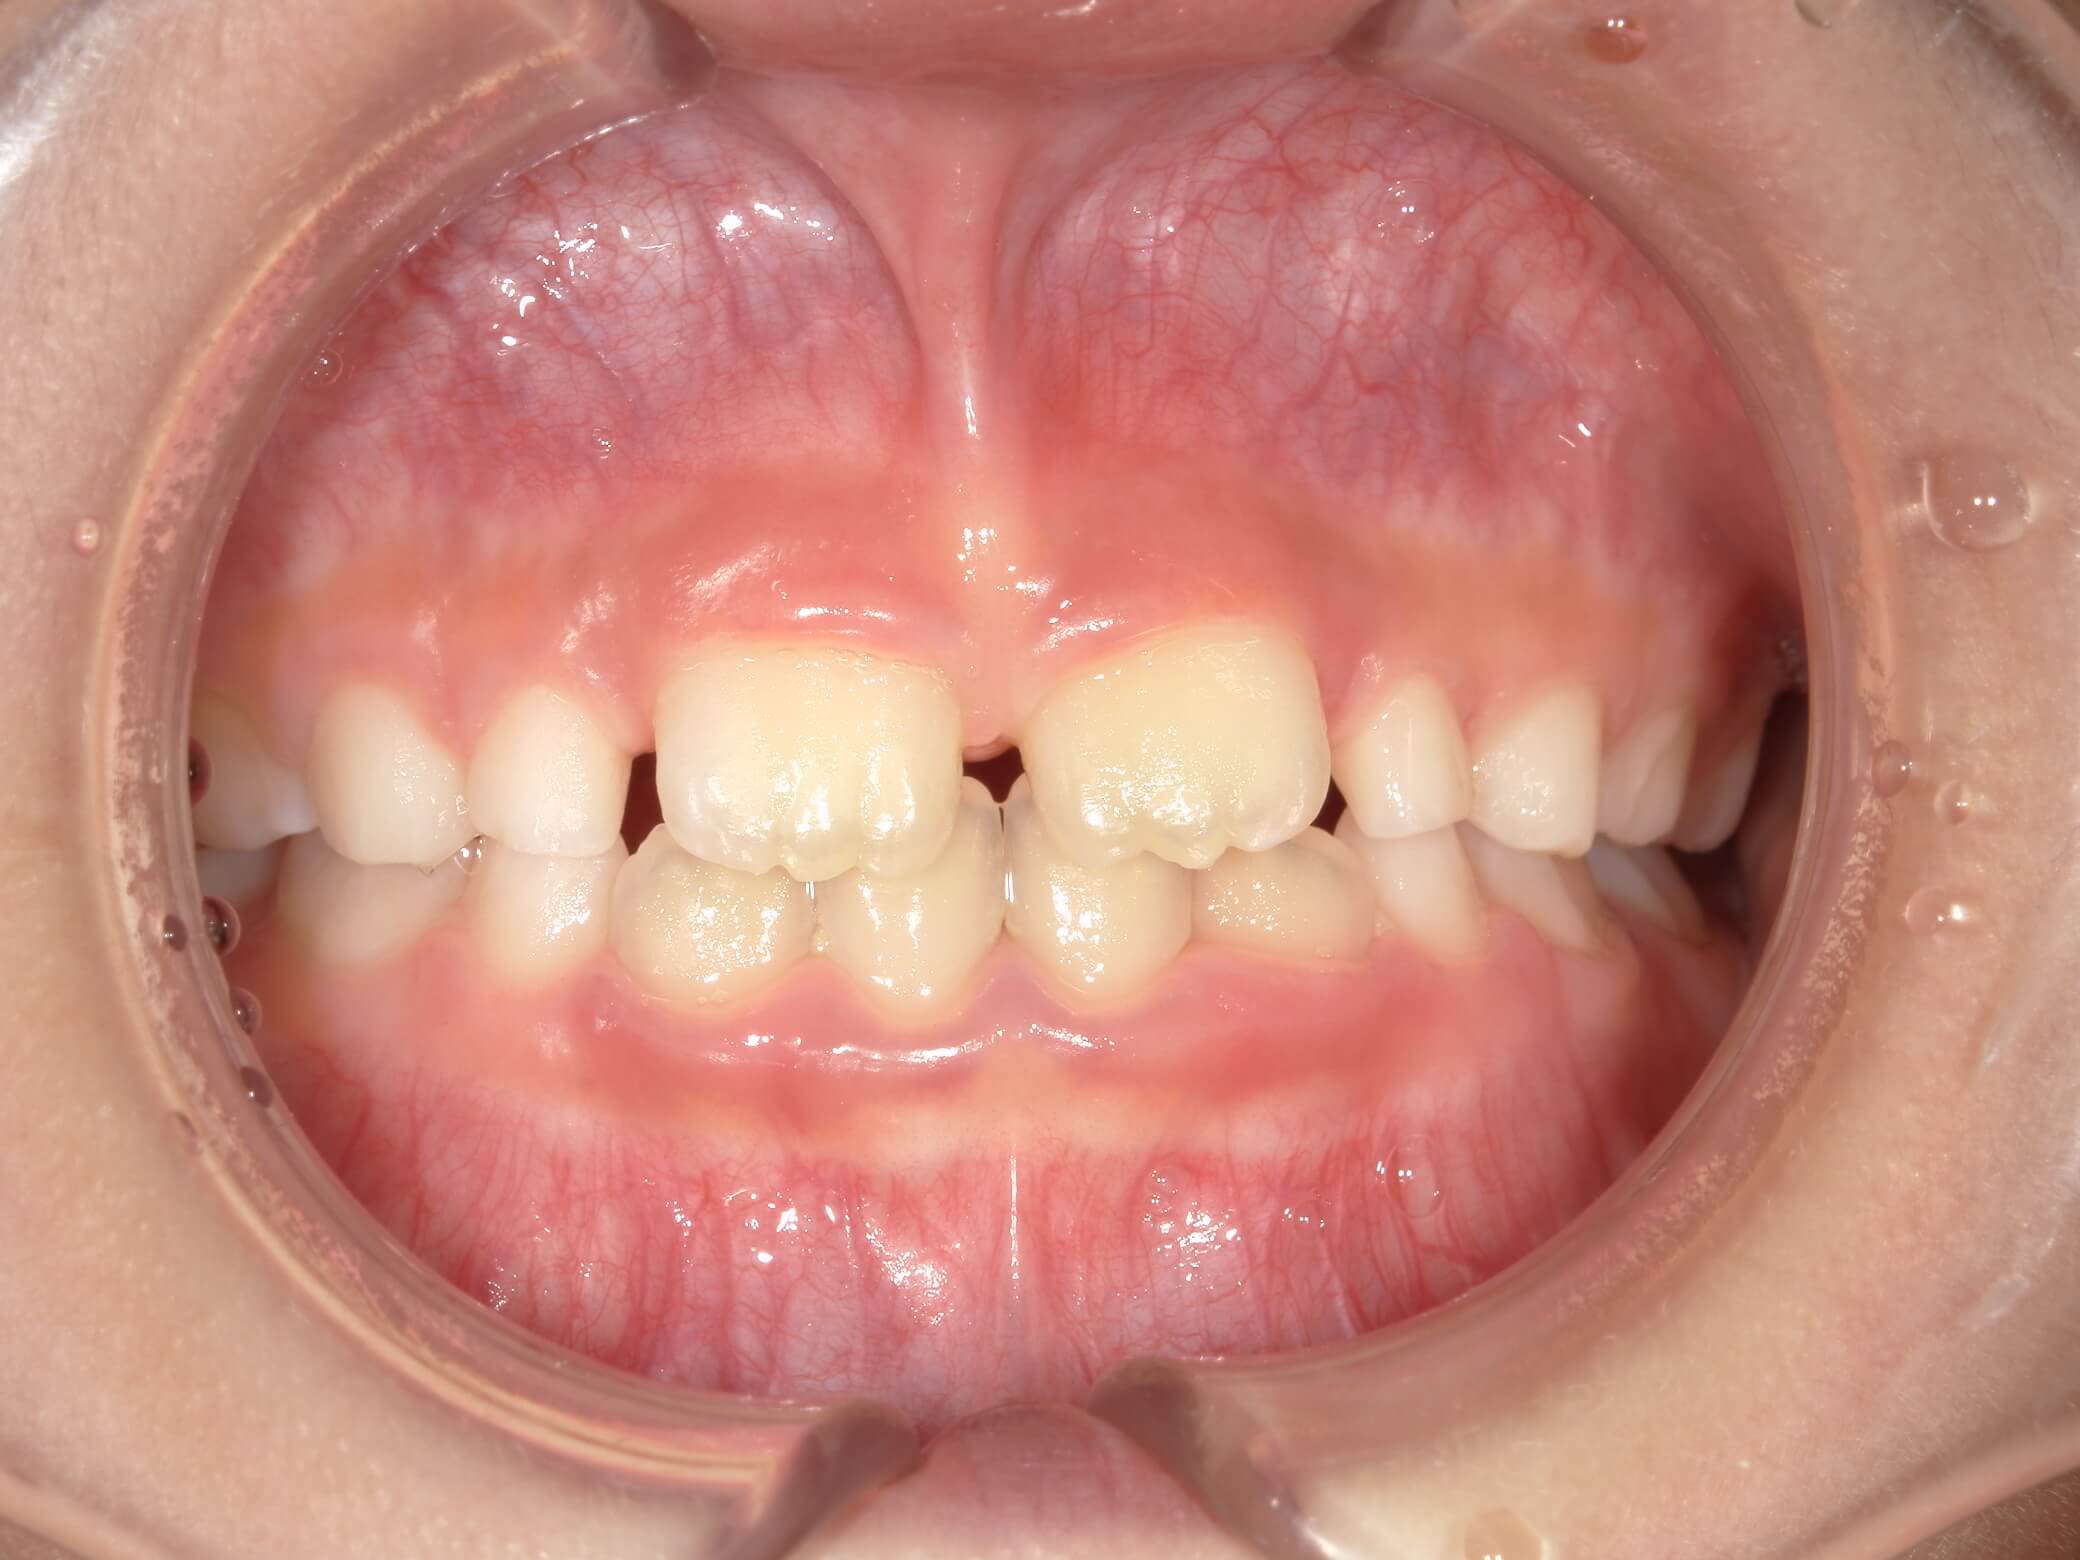

| 年齢・性別 | 8歳11ヶ月の男児 |

|---|---|

| 主訴 | 上顎の永久歯の位置がおかしいとのことで来院。萌出していない右上の前歯の状態に不安を抱えられていました。 |

| 治療期間・回数 | 約3年2ヶ月 |

| 費用 | 440,000円(税別) |